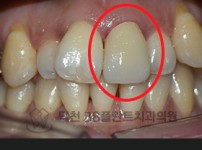

치료전후